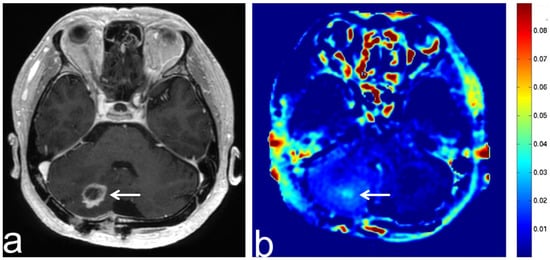

7.3. Schwannoma